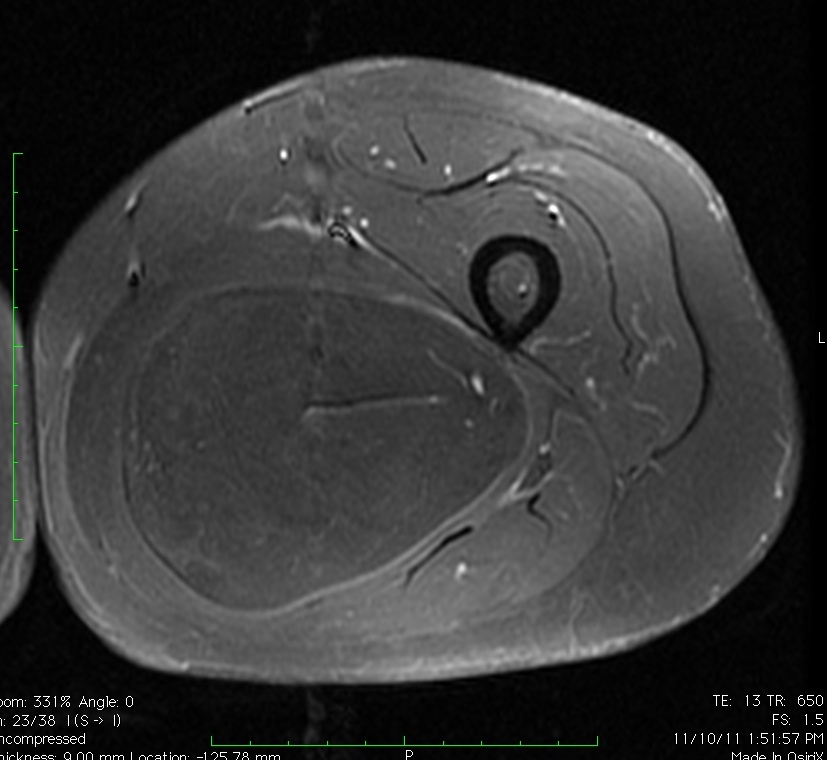

MRI

• Follows the signal characteristics of subcutaneous fat on all sequences

• T1: High Signal

• T2: Intermediate Signal; Low Signal with Fat Suppression

• Minimal or No enhancement with gadolinium

Fig. 1A, 1B, 1C, 2A, 2B, 2C: MRI of a lipoma: T1- weighted images shows an homogeneous mass in the posterior compartment of the thigh with high signal, saturates on fat saturated sequences with no or minimal enhancement. On T2-weighted images demonstrate an intermediate signal on FSE T2, saturates (becomes dark) on fat saturated sequences.